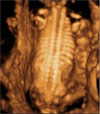

Este feto presenta una anomalía esquelética clara, con costillas muy cortas, que no permiten un desarrollo adecuado del tórax y de los pulmones fetales. Muchos de estos bebés mueren al nacer por ser incapaces de respirar.

Ecografía Embarazo 2D y 3D - TERCER TRIMESTRE: Malformaciones fetales